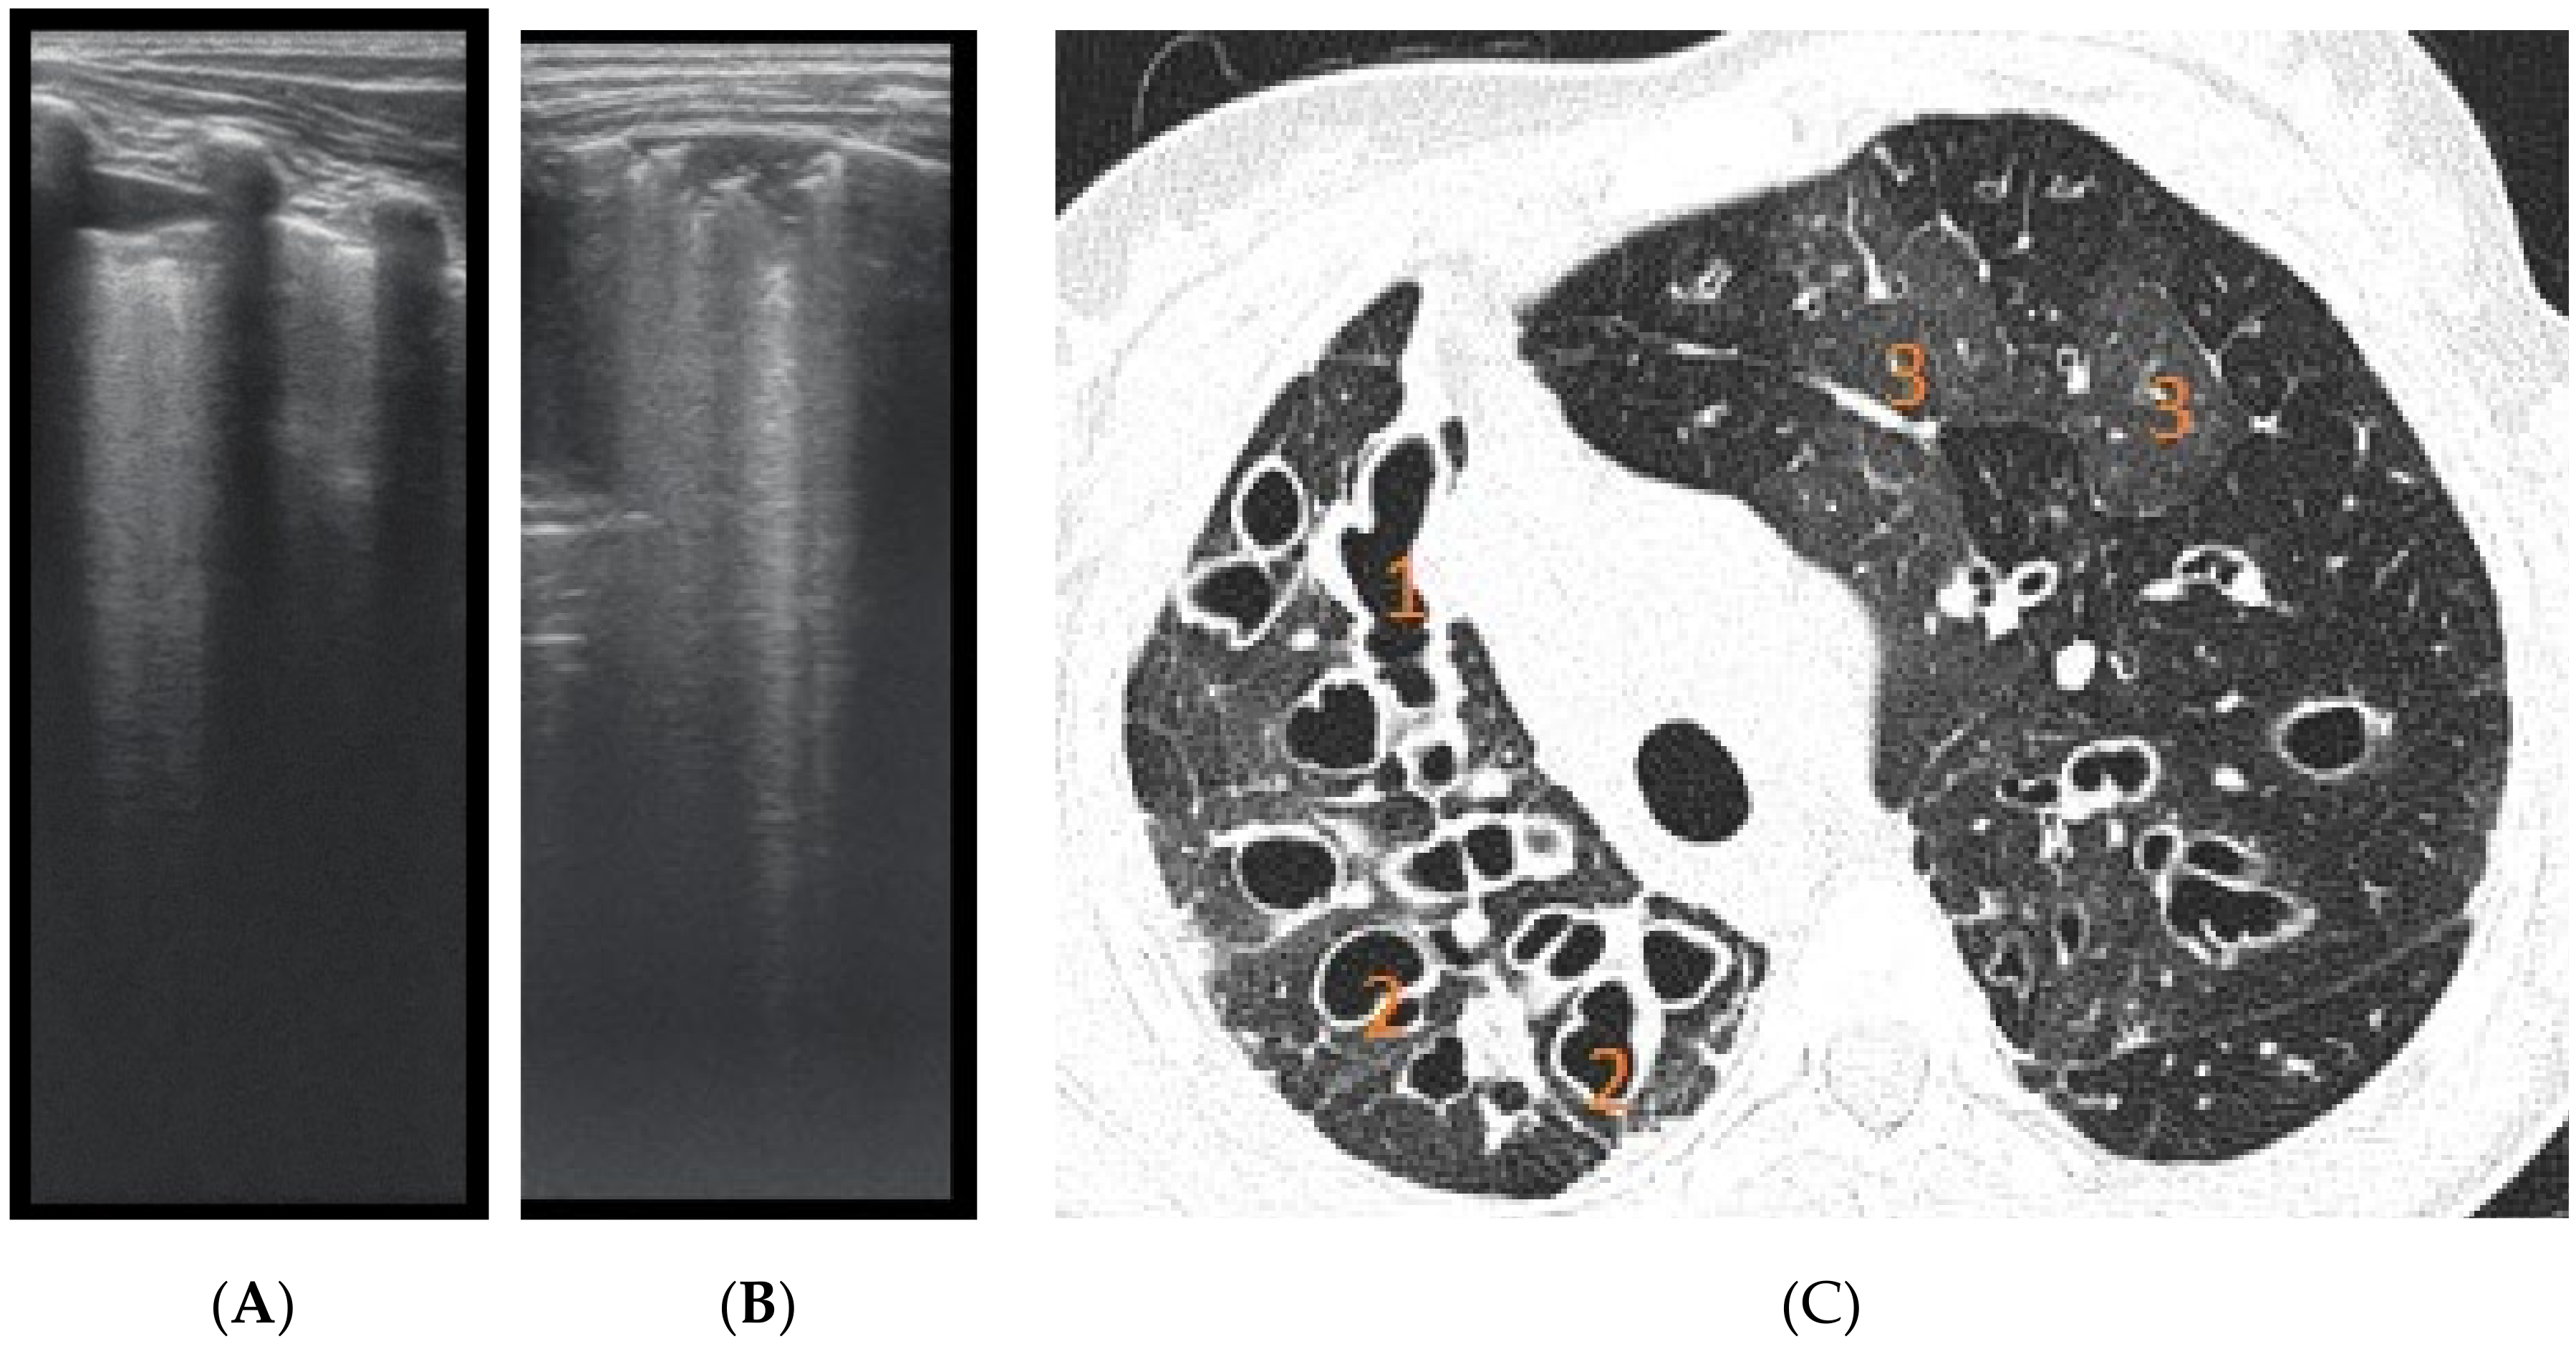

The artefacts used to define the pathological elements were as follows (Table 1): the presence of A lines—normal aspect = 0 points; less than 3 B lines, thin (< 2 mm in width)/intercostal space = 0 points; more than 3 distinctive B lines or 1 coalescent B line = 1 point, quantifying interstitial inflammation or small bronchiectasis (Figure 1) confirmed by CT (Figure 2); more than 2 coalescent B lines = 2 points, suggestive of alveolo-interstitial inflammation or mucus plugging with loss of aeration; either bronchial wall thickening or subpleural consolidation < 1 cm = 3 points, associated with the absence of A lines quantified either as small atelectasis or cystic bronchiectasis with mucus plugging; subpleural lung consolidation > 1 cm, without bronchogram = 4 points; quantified atelectasis (Figure 3)/consolidation with bronchogram = 5 points.

The right hemithorax of the same patients revealed the presence of B lines for cylindrical bronchiectasis via LUS (Figure 5).

Figure 1. LUS image shows B lines > 3, LUS score = 2. The corresponding CT image (Figure 2) shows bronchiectasis.

Figure 2. CT reveals (1) peripheral cylindrical bronchiectasis with mucus plugging.

Figure 5. LUS: coalescent B lines, with a very small subpleural consolidation (2 points) and 2 coalescent B lines (2 points), corresponding to mucus-filled varicose bronchiectasis; examination of the same patient’s right posterior hemithorax.

Figure 7. (A) LUS: coalescent B lines, erased A profile, loss of aeration, left hemithorax. (B) LUS image with subpleural consolidations, coalescent B lines, and left hemithorax. (C) CT scan of the same patients: (1) varicose bronchiectasis with middle 1/3 of lung extended and moderate bronchial wall thickening; (2) saccular bronchiectasis with mild and moderate wall thickening; and (3) zones with increased attenuation of pulmonary parenchyma (alveolar infiltrates).